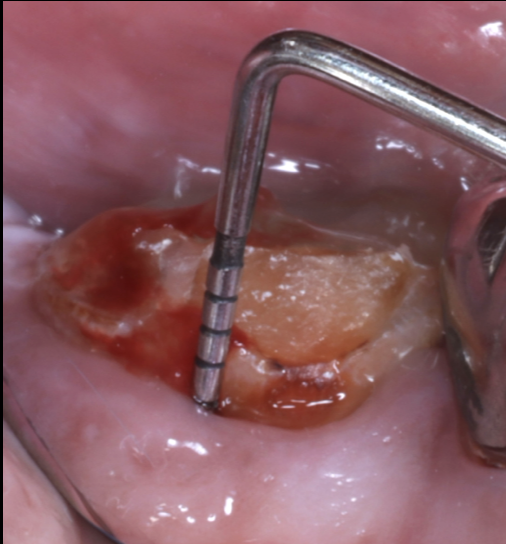

折れた歯を残す「エクストルージョン」という選択...